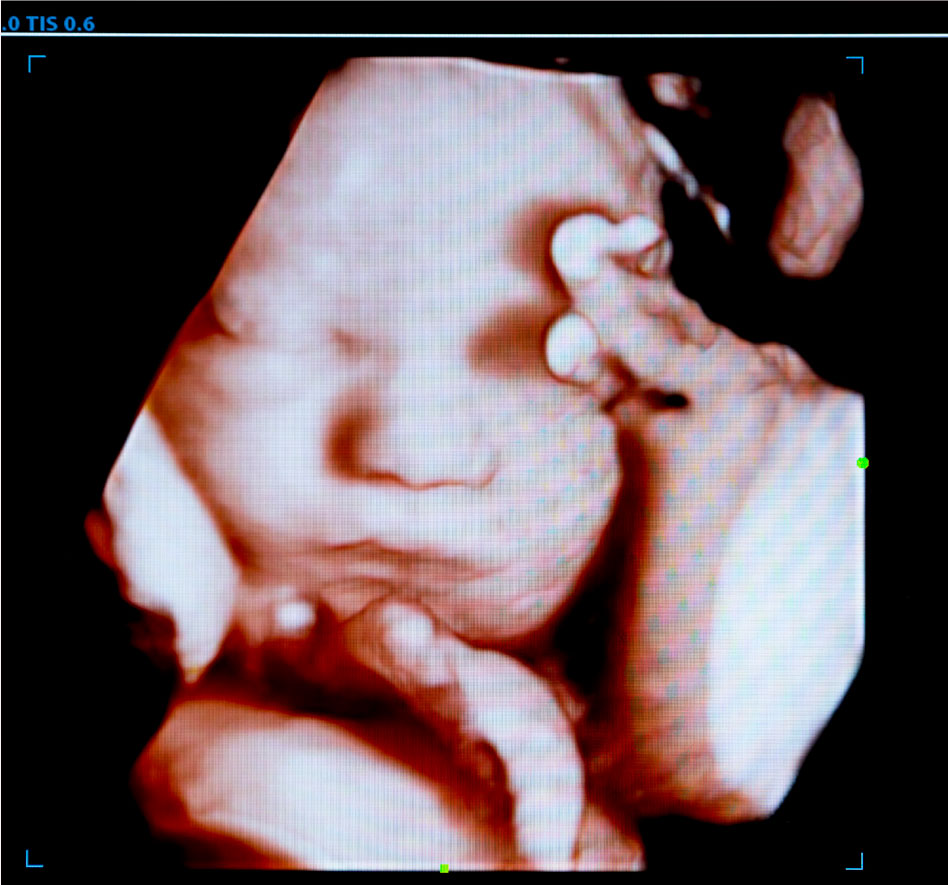

- LCCC offers 3-D/4-D technology and will attempt to obtain beautiful images for keepsakes. The quality of the images obtained will depend on the baby's position and cooperation.

- LCCC students will provide volunteers with printed paper images from the session.

- LCCC students will provide volunteers with a USB with images from the session.